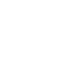

Una ecografía en 3D o tridimensional es una técnica de diagnóstico por imagen que utiliza ondas sonoras para crear imágenes detalladas del interior del cuerpo, especialmente de órganos o estructuras en desarrollo, como un feto en el embarazo. A diferencia de la ecografía tradicional en 2D, la ecografía en 3D proporciona una visualización más realista y detallada, permitiendo ver la forma, tamaño y posición de los órganos o el bebé desde diferentes ángulos. Esta tecnología es comúnmente utilizada en obstetricia, pero también puede aplicarse en otras áreas médicas.

La ecografía 3D nos permite obtener una imagen tridimensional del útero, ovarios, trompas de falopio y vagina. Su importancia radica en la aportación del tercer plano, lo que supone un cambio sustancial en el estudio de los órganos de la pelvis femenina, ya que es posible observar y analizar volumétricamente tales órganos (en tiempo real si se trata de 4D).

Este examen permite el estudio de malformaciones uterinas, patologías de la cavidad del útero (pólipos, miomas, tabiques, etc), quistes o tumoraciones en los ovarios.

⚛ Ecografías 2D-3D